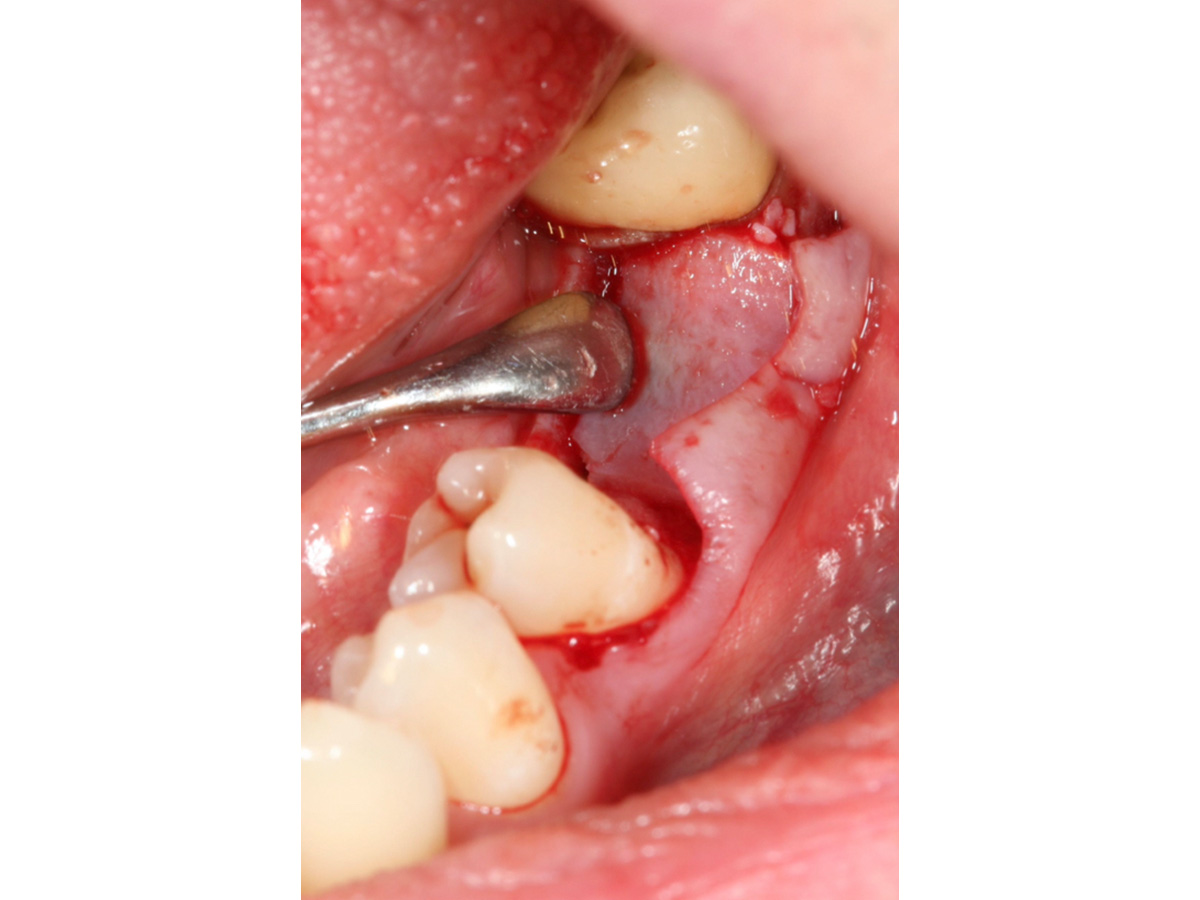

Abb. 8 zeigt die Situation vor dem Freilegen des Implantates und Abb. 9 die erfolgreiche Augmentation fünf Monate post operativ. Zu erkennen sind zwei Pins, deren Position sich im Niveau der Augmentation befinden und damit verdeutlichen, dass es zu keiner Resorption des ursprünglichen Augmentationsniveaus gekommen ist.

Situation vor dem Freilegen des Implantates.

Abbildung 9

Augmentation nach fünf Monaten (klinisch).

Abbildung 10

Augmentation nach fünf Monaten (röntgenologisch).